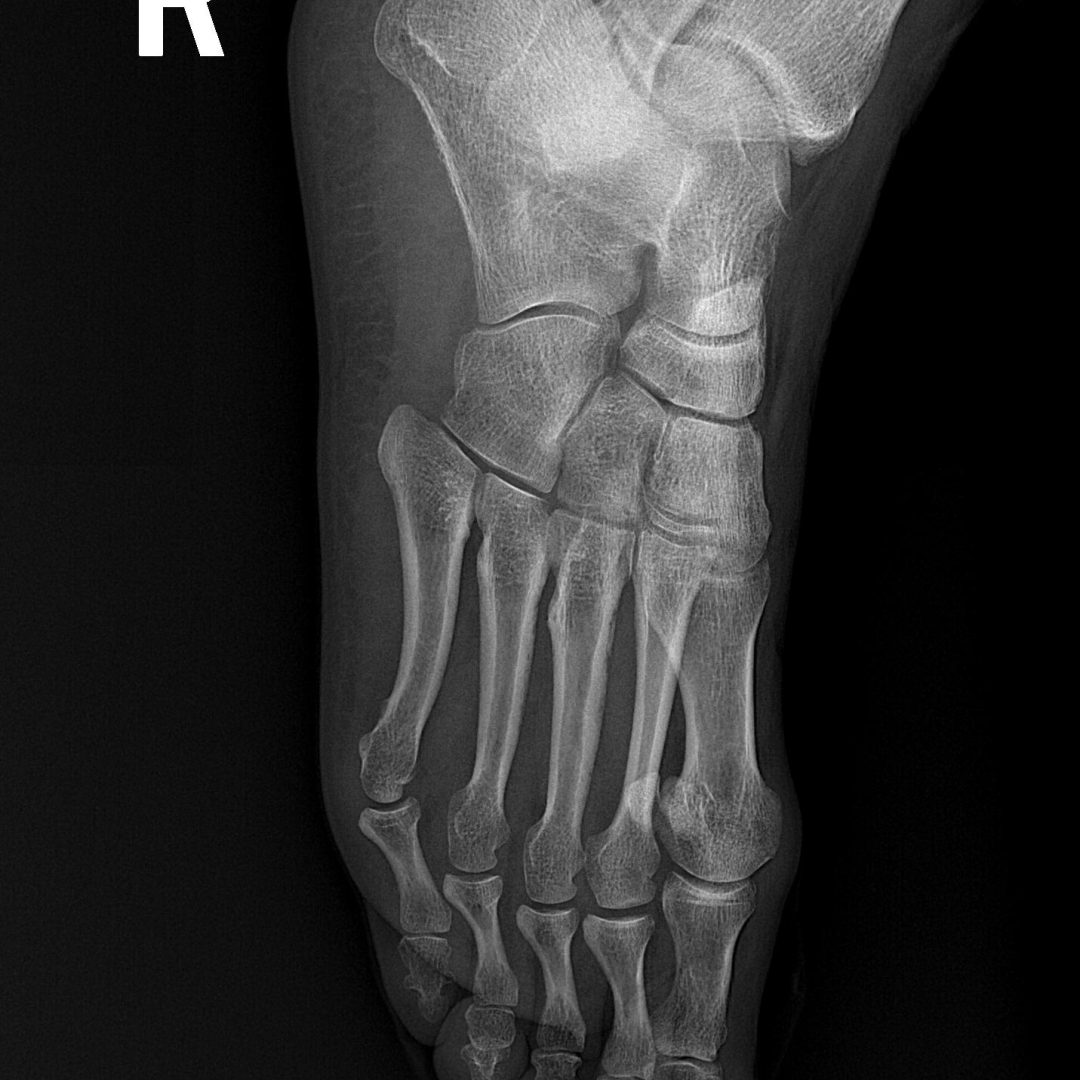

患者: 女性,45岁 -

初诊日期: 2025年1月25日

患者主诉其右踝于2024年12月15日下楼梯时摔倒受伤,随后进行了石膏固定,并一直采取保守治疗至今。目前使用拐杖+行走靴辅助行走,下台阶时外踝疼痛。 -

踝关节及第一跖趾关节 (1st MTR) 活动度受限,患者抗拒跖屈。

触诊: 足底筋膜紧张;小腿三头肌萎缩伴胫骨后肌压痛;跟骨和距骨活动受限。